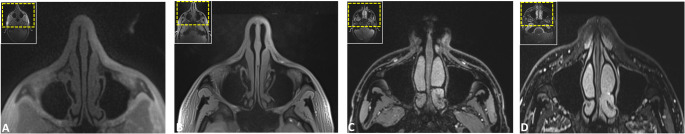

Methods: In this prospective study, healthy volunteers underwent 3T MRI using five protocols: DESS, SPACE STIR, SPACE SPAIR, T1-VIBE Dixon, and UTE. Eight trauma-prone regions, including the nasal septum, orbit, naso-orbito-ethmoidal (NOE) complex, zygomaticomaxillary complex, Le Fort regions, mandible, condyle, and dentoalveolar complex, were assessed. Image quality, artifacts, anatomical delineation, and bone-to-soft-tissue contrast were rated on a five-point Likert scale by three independent observers. Descriptive statistics and inter-rater agreement (intraclass correlation coefficients (ICCs)) were calculated.

Results: Sixteen participants (37.2 ± 12.9 years; 12 males, 4 females) were included, resulting in 80 MRI volumes and 640 regions for evaluation. UTE and VIBE-DIXON sequences achieved the highest ratings for image quality, artifact susceptibility, and anatomical delineation across most fracture-prone regions (ICC: 0.793-1; all p < 0.001). UTE excelled in visualizing NOE and Le Fort regions, while VIBE-DIXON performed best in mandibular and orbital imaging. Bone-to-soft-tissue contrast was highest in UTE and VIBE-DIXON, highlighting their diagnostic potential in simultaneous soft and hard tissue imaging. Inter-rater agreement was consistently high (ICC: 0.772-0.976; all p < 0.001).